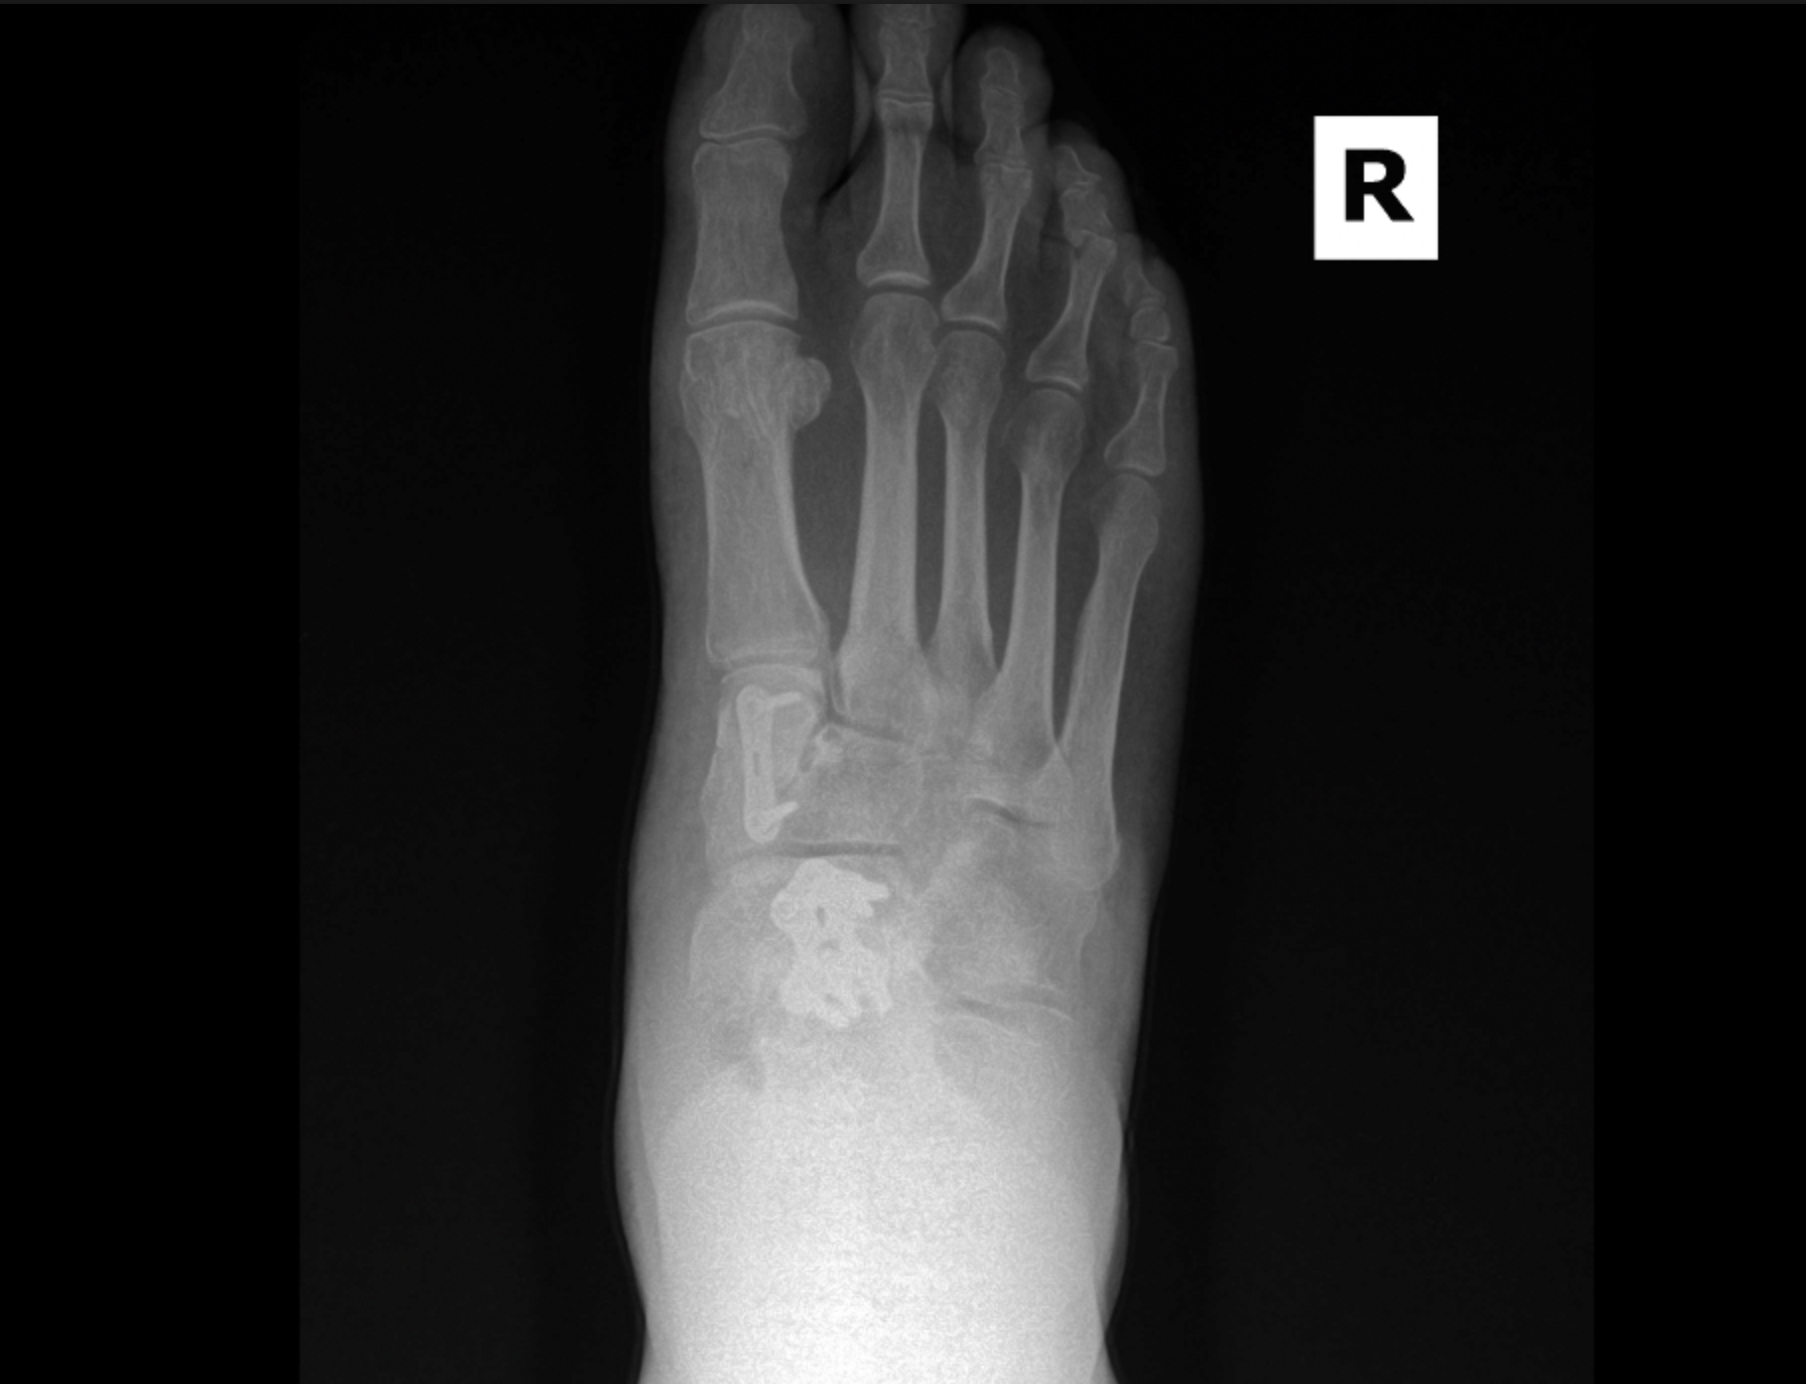

MIS Bunion

MIS3

MIS2